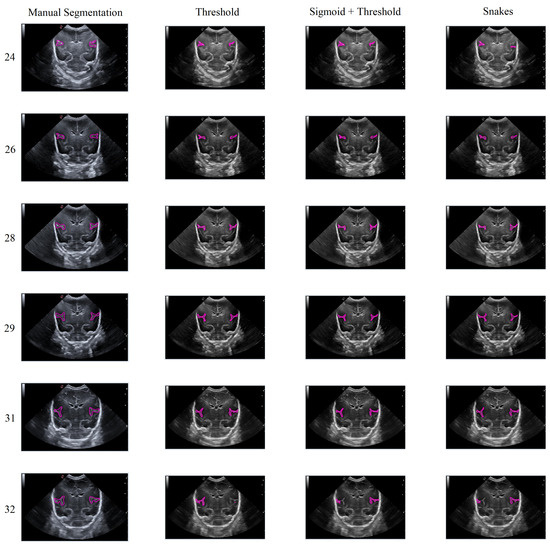

In general, the results obtained from the semiautomatic process have been mostly accurate with good precision, except in cases where the noise was too high, making it difficult to identify and define the groove. Nevertheless, the defined algorithm largely fulfills its objective, allowing for modifications to be made to the segmentation results without having to execute the algorithm again. An example of this can be seen in Figure 15, which displays different samples of segmentation on the Sylvian furrow and how it evolves throughout several weeks of gestation in a baby. The figure shows the manual slicer, Threshold, Sigmoid + Threshold, and Snakes algorithms in the columns from left to right. Each row represents the week of gestation when the ultrasound was taken (from top to bottom: 24, 26, 28, 29, 31, and 32).

Figure 15. Segmentation examples for the Sylvian sulcus (Manual segmentation), carried out between weeks 24 and 32 of gestation of a mime baby applying the different segmentation methods (Threshold, Sigmoid + Threshold, and Snakes).